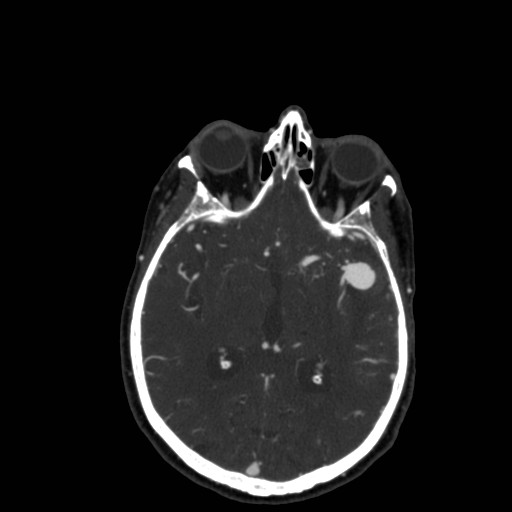

45 year old female presented with right arm weakness and a Head CT with and without contrast was performed. CT demonstrates subarachnoid hemorrhage with a left MCA aneurysm.

| Image 1 - Non Contrast CT | Image 2 - CT Angiogram | Image 3 - CTA 3D Reformat |